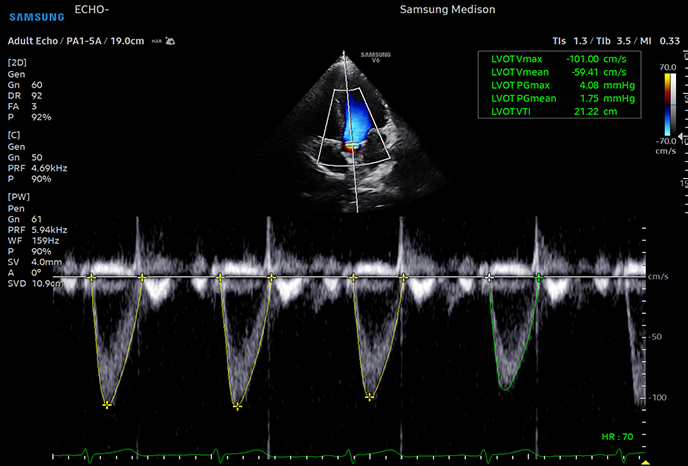

하이앤드 초음파 장비를

활용한 정밀 심장 검사

심장 질환 진단에서 가장 중요한 것은 ‘심장의 상태를 얼마나 정확하게 볼 수 있느냐’입니다. 저희 센터는 대학병원급 하이앤드 초음파 장비를 도입하여, 실시간 3D 렌더링으로 정밀 진단이 가능하며, 심장의 구조·혈류·기능을 실시간 고해상도로 관찰합니다.

미세한 판막 움직임, 혈류 속도 변화, 심방·심실 크기와 수축력까지 정밀하게 분석할 수 있어, 심장질환의 조기 발견과 치료 계획 수립에 큰 차이를 만듭니다.